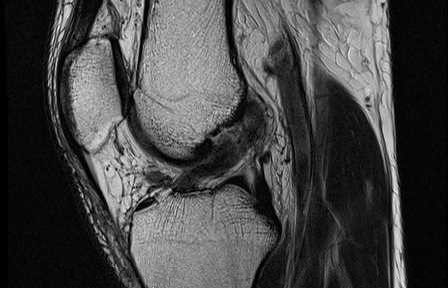

Natural Healing of an ACL tear – Healed Case 29

Natural Healing of a Complete ACL Tear in Children – Case 24

Natural Healing of a Complete ACL Tear – Case 19

ACL Tear Self Healing – Case 18